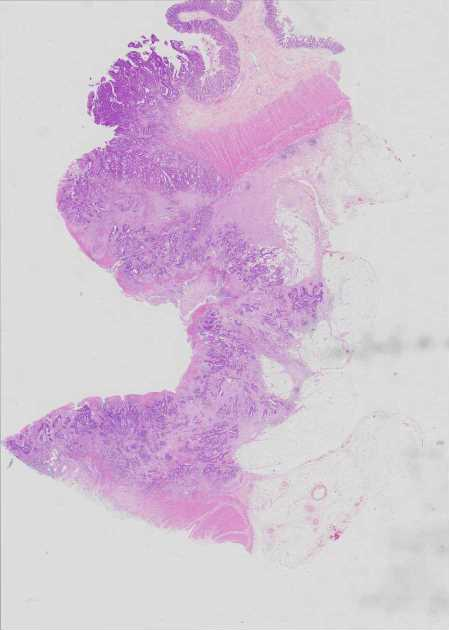

Use Case 3

041730593781

Overview Statistics B details